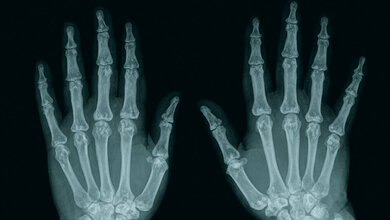

Anomalien und Normvarianten: Skelettale Veränderungen 3.29: Brachydaktylie und Brachymetacarpie

Die Brachydaktylie ist Teil einer Gruppe der Gliedmaßen-Malformationen mit Knochendysostosen. Die isoliert auftretende Brachydaktylie ist selten. Sie kann mit anderen Fehlbildungen der Hand einhergehen, wie zum Beispiel Syndaktylie oder Polydaktylie.

Schlüsselwörter: Brachydaktylie, Röntgen, CT, MRT